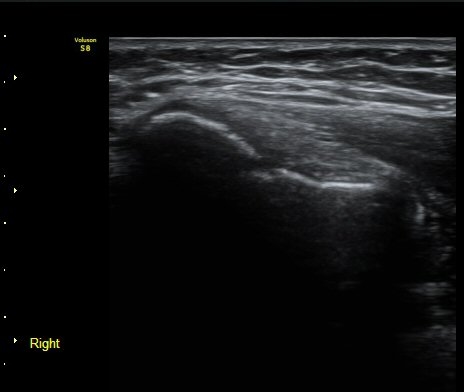

³»»ó°ú Á¾´Ü¸é°Ë»ç»ó  ³»ÃøºÎÀδë Àú¿¡ÄÚ ºÎÁ¾°ú ³»»ó°ú ÀÎ´ë ºÎÂøºÎ ÇÇÁú°ñÀÇ ºÒ±ÔÄ¢º¯È­¿Í

°ñÆíÀÌ °üÂûµÇ°í(±×¸² 1, 2, 3, 4) ÀÌ·±¼Ò°ßÀº °ÇÃø°ú ºñ±³ÇÏ¸é ´õ¿í ¶Ñ·ÈÇÔ(±×¸² 5, 6).